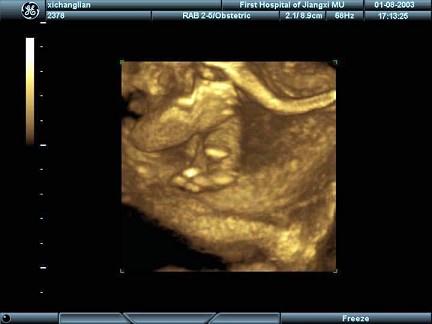

女性,25岁,停经35周。产前超声检查,图像显示的是胎儿的?(?)A.脊柱B.肢体C.颜面部D.胸腔E.胎头

问题 女性,25岁,停经35周。产前超声检查,图像显示的是胎儿的?(?)

选项 A.脊柱 B.肢体 C.颜面部 D.胸腔 E.胎头

答案 B